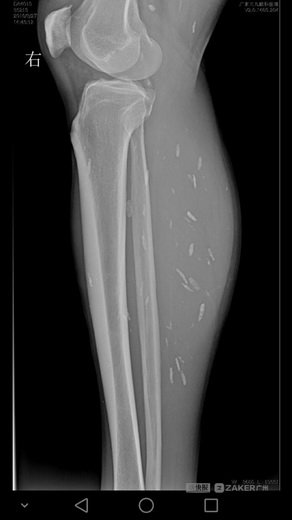

刘宇的小腿 X 光片显示下肢也有囊虫。

今年3月,刘宇连续两周头痛剧烈,走路不平稳,遂去广东三九脑科医院就医。据该院神经外六科主任吴杰介绍,患者的影像检查提示颅内多发占位病变,结合病史,考虑为颅内多发脑囊虫病。完善相关检查后,近日,吴杰主任为患者在全麻下行 " 左侧小脑囊虫占位切除术 "。术后病理提示为脑囊虫病。除了头部,影像检查还提示,患者双下肢也有囊虫。